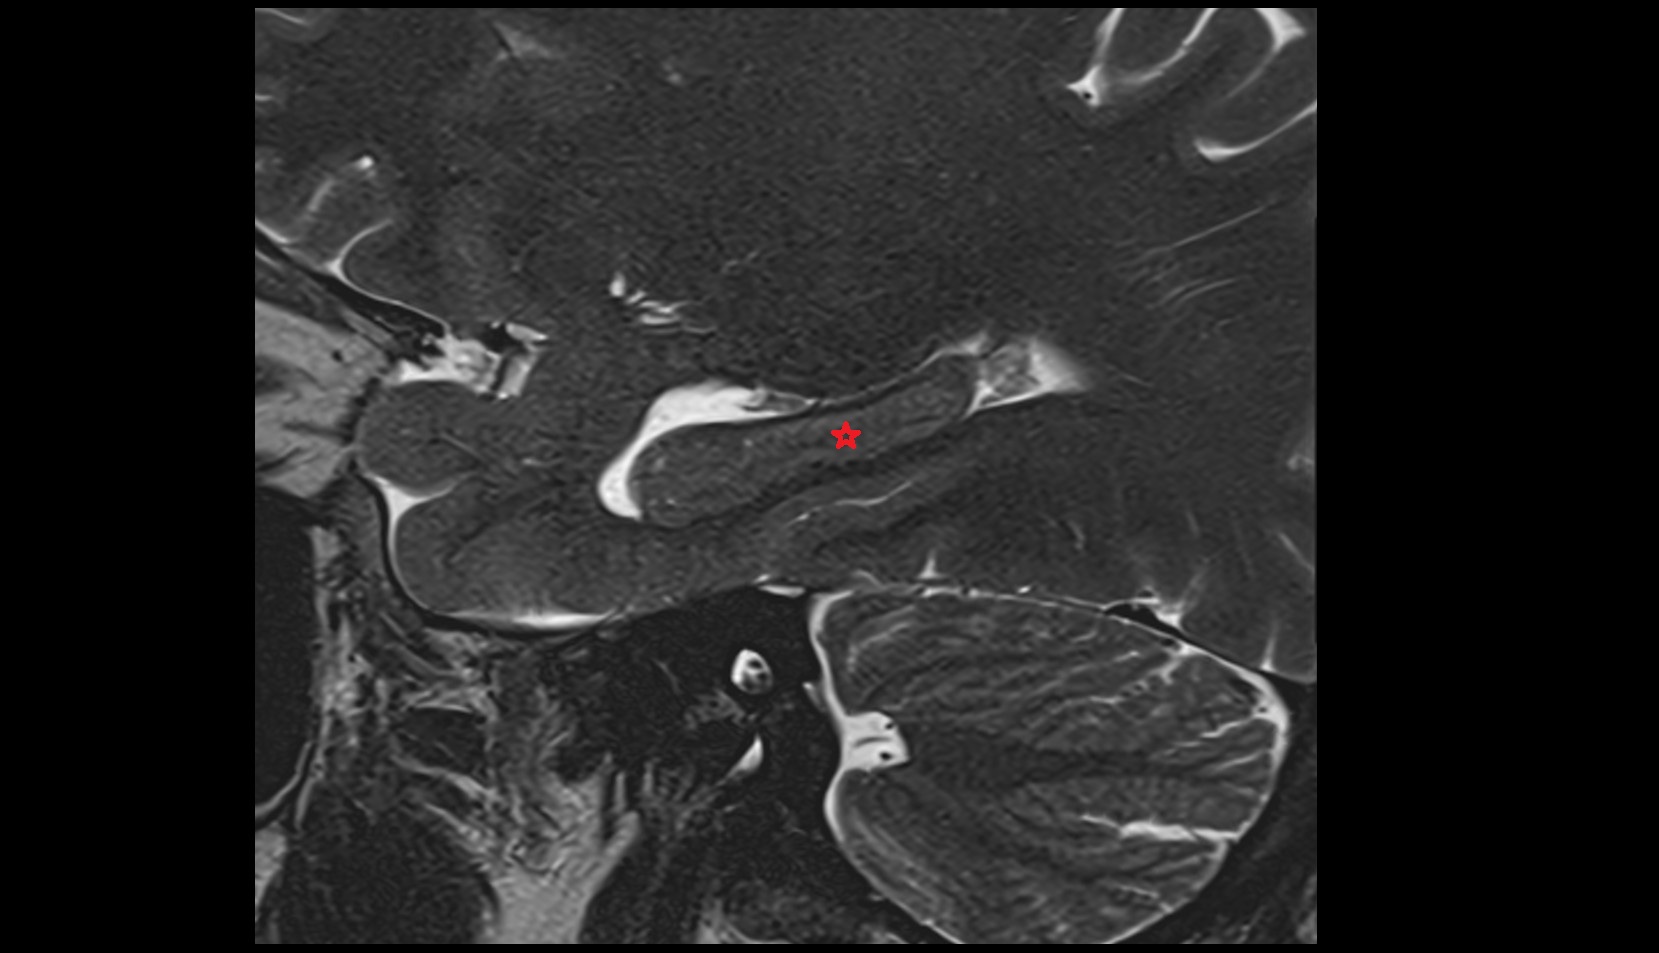

- Temporomandibular joint

- Articular disc of temporomandibular joint

- Articular eminence

- Mandibular condyle

- Mandibular fossa

- Superior head of lateral pterygoid muscle

- Inferior head of lateral pterygoid muscle